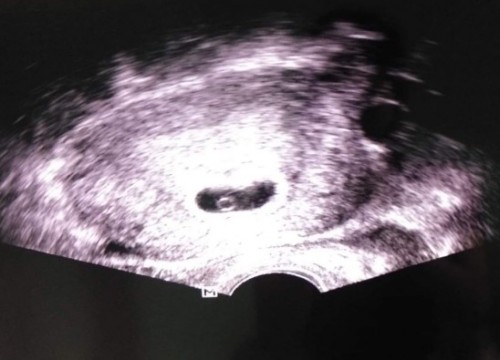

9w ค่ะ